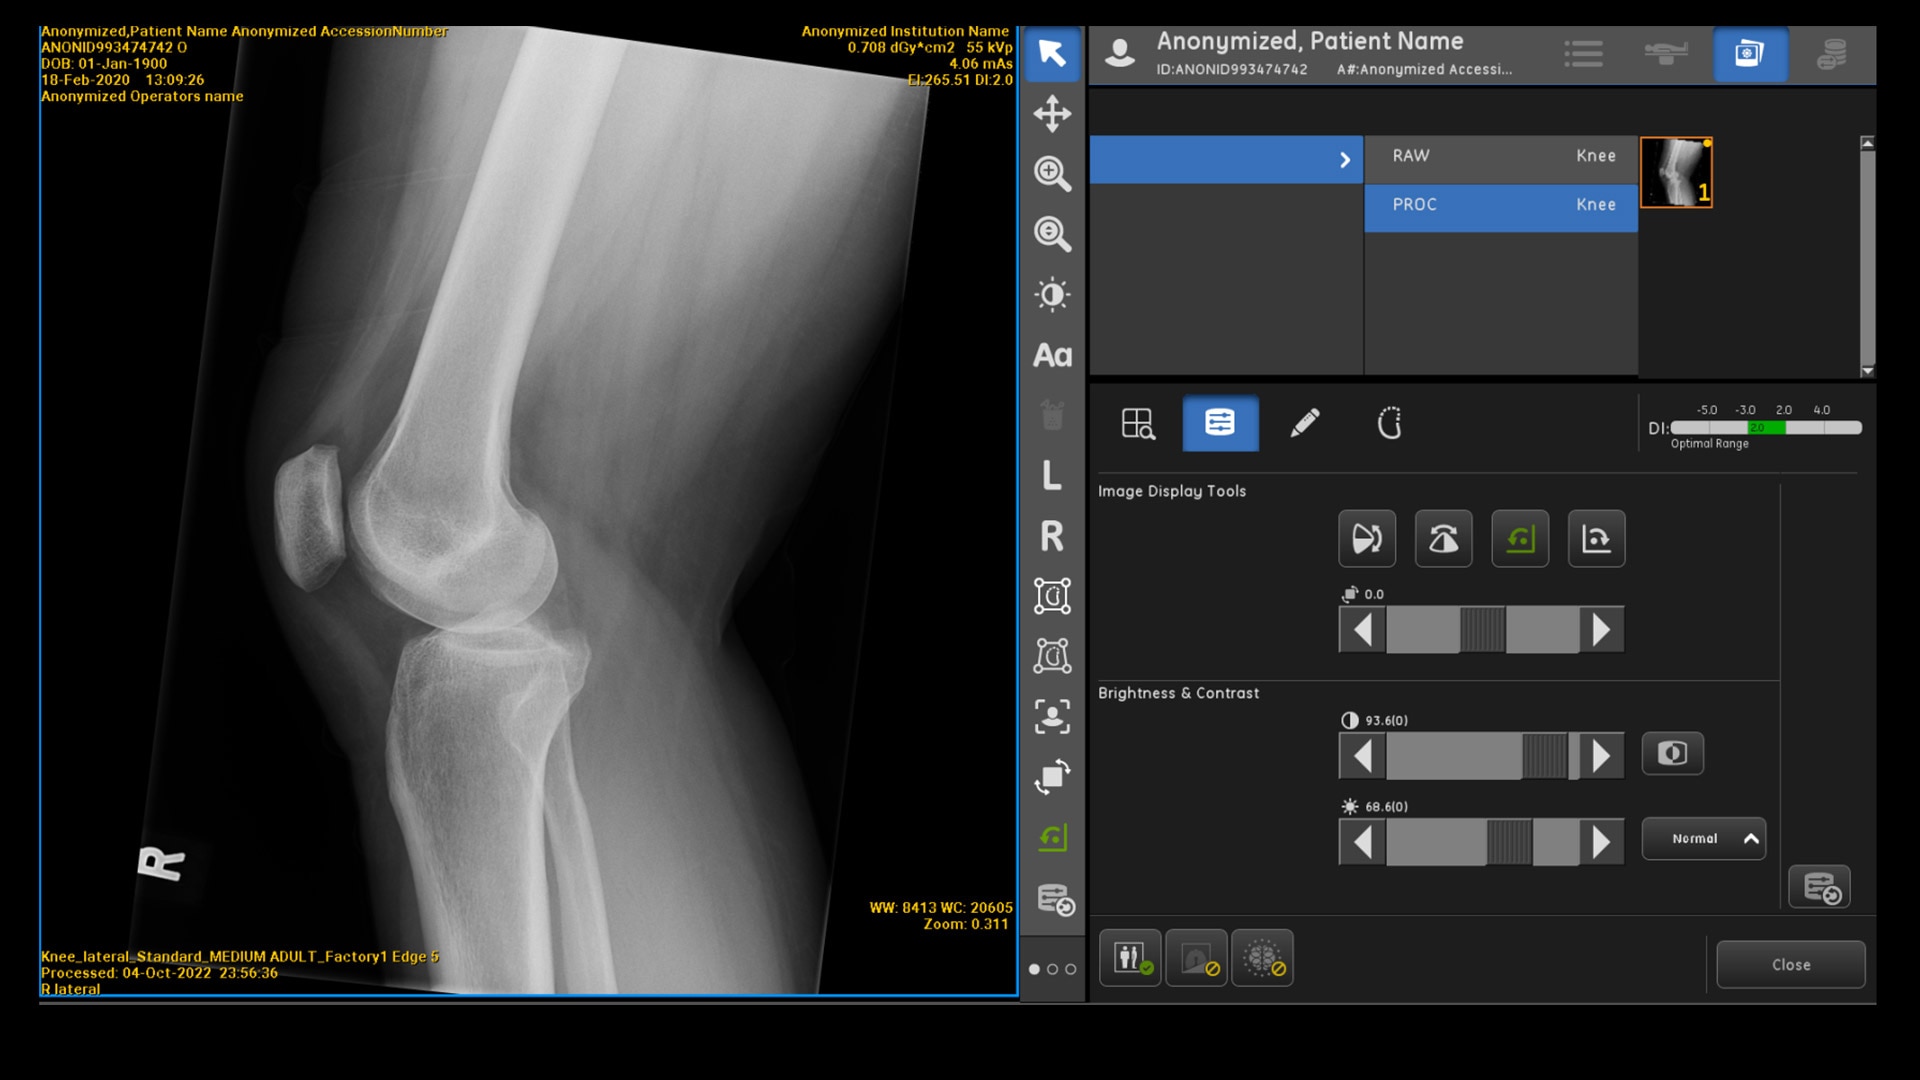

85% COMPREHENSIVE COVERAGE1,3

AI that goes beyond chest

X-rays

For the first time, our GE Healthcare AI offering includes support for pediatric patients. Auto-rotation is available for the most frequent X-ray exams, including babygrams, chest, abdomen and pelvis exams for both pediatric and adult patients. Additionally, it’s available for hand, wrist, foot and knee exams for adult patients.1,3